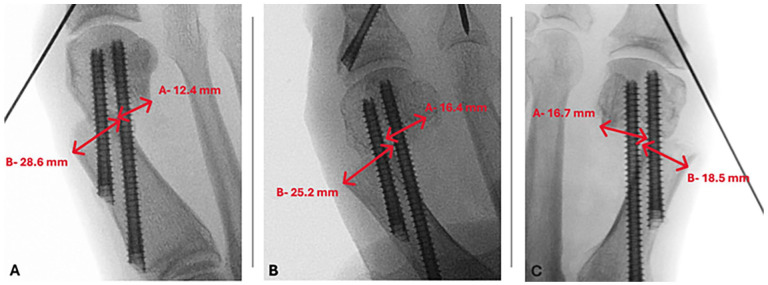

Methods: We retrospectively analyzed 217 consecutive patients with moderate to severe hallux valgus who underwent fourth-generation MIS first distal metatarsal and Akin osteotomy between 2020 and 2023 and were followed for up to 1 year. Radiographic measurements included the scale of displacement between the proximal and distal portions of the first metatarsal as a percentage and the number of neocortical bridge formations at the osteotomy site. Postoperative weightbearing radiographs were recorded at 6 weeks, 3 months, 6 months, and 1 year to assess time to union and patient clinical outcomes. Two orthopaedic surgeons independently reviewed the radiographs to assess progression to bony union. Any discrepancy in analysis was resolved by a third-party clinician. Complete union was defined as the presence of at least 2 new cortical bridge formations on postoperative X-ray films. Patients were divided into 3 groups based on the percentage of shift on the first metatarsal head (≤50%, 51%-75%, ≥76%) for the purpose of our analysis.

Results: Union (≥2 cortices) was observed in 17%, 70%, and 90% of patients at 6 weeks, 3 months, and 6 months, respectively. At final follow-up (mean 13 ± 6.9 weeks), 92% achieved union. No significant differences in time to union were observed across metatarsal shift groups.Complications include 3 nonunions, 3 revisions, 16 cases that necessitated removal of hardware, 1 case of superficial wound infection, 1 case of deep wound infection, and 6 deformity recurrences.